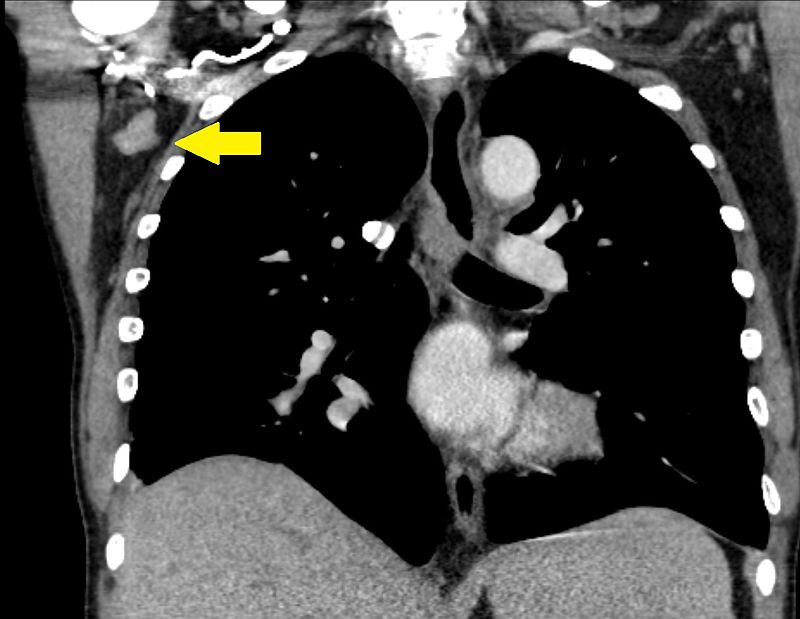

Patients with Hodgkin lymphoma (HL) typically present with enlarged cervical or mediastinal lymph nodes.

- Nodular sclerosing (has bands of fibrosis cross lymphoid tissue)